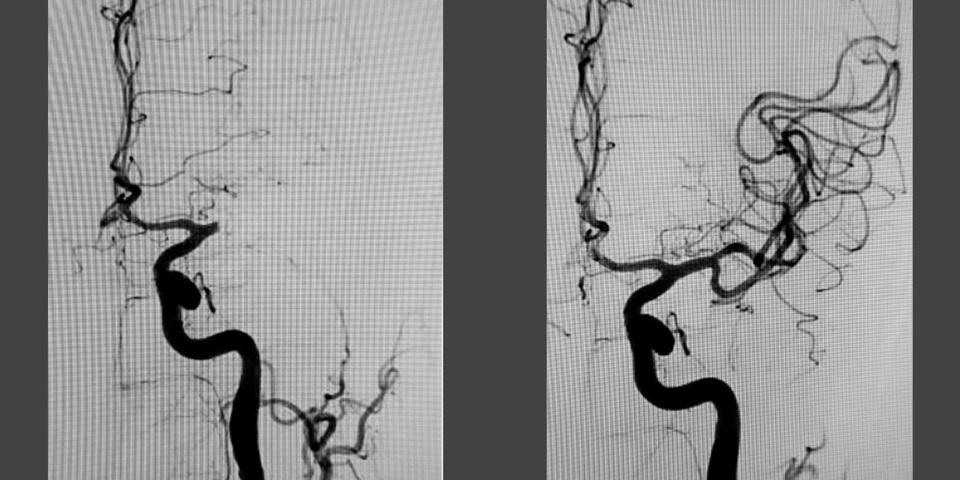

Scanningsbilleder af hjerne, før og efter en blodproppen er blevet opløst.

Når en hjerne scannes ses blodårene som sorte streger. Her er det tydeligt, at en blodprop har sat sig fast, for blodforsyningen stopper pludseligt. Her ses den samme hjerne, men blodproppen er fjernet, og blodforsyningen er genetableret.